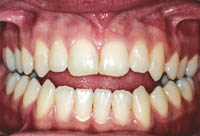

Antes

DepoisUm belo sorriso é capaz de conseguir qualquer coisa e tocar fundo os corações. Assim, qualquer investimento que você faça em sua boca e face, a longo prazo, torna-se um custo irrisório.